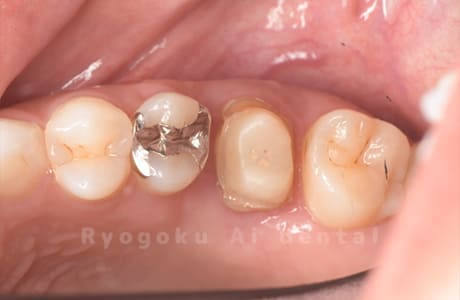

Case14

-

- 抜歯原因

- 重度カリエス

- 治療内容

- クラウンレングスニング治療

- 治療費用

- 44,000円

他院で抜歯と言われた、とのことでご来院された患者さまです。クラウンレングスニングを行い、保存致しました。大変満足して頂けました。

<リスク・副作用>

治療後、痛みや違和感、出血、腫れなどが出る事があります。喫煙者、糖尿病などの方の場合、歯が生着しない場合があります。